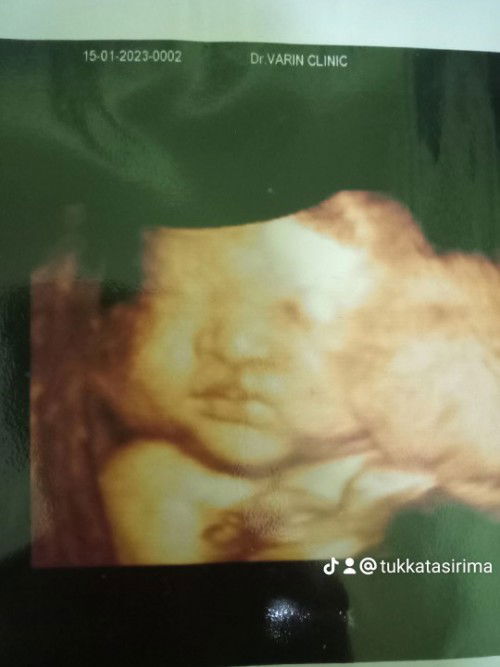

39w3dไม่มีทีท่า..โดนกระตุ้นปากมดลูกไปเลยสิค่ะทีมมีนาคม#ลูกสาว